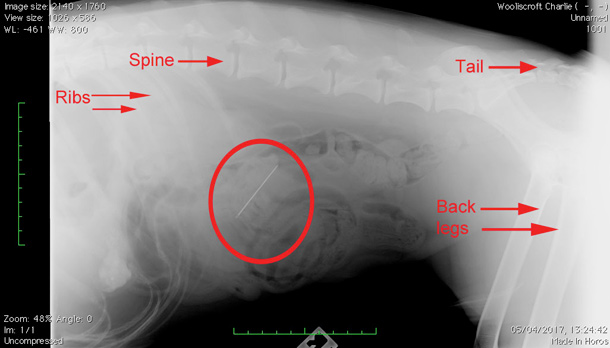

A lovely springer spaniel called Charlie was brought down to us by his owners having been sick a couple of times. Our vet Eve decided to take an X-Ray of his abdomen to see if we could find a reason for his illness. Often in our job it is an exercise in detection - can we find out the cause of a particular problem using a few tests as possible in order to minimise intervention with the pet and cost to the owner’s wallet! Most of the time several tests are required before it becomes clear what is going on. In Charlie’s case however, it was perfectly obvious from the first X-Ray - he had eaten a sewing needle! You can see it there on the X-Ray - metal shows up white on X-Rays and there it is clear to see, you can even make out the ‘eye’ of the needle on the left end of it!